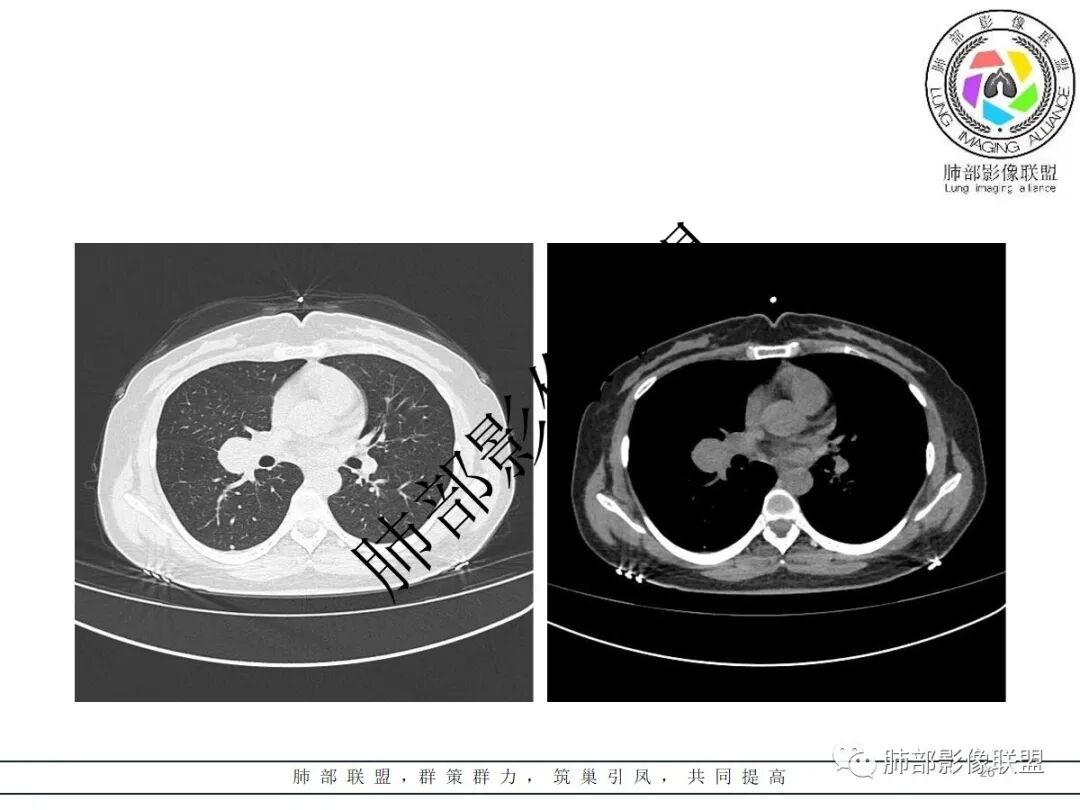

右肺门类圆形实性肿块,边缘光滑,无分叶毛刺,跨叶,推移血管,密度均匀,增强延迟强化相对明显,未见坏死及血管造影征。

2.右肺水平叶裂斜叶裂肺门交界区类椭圆形块影,表面光整,未见分叶毛刺及棘状突起,未见邻近结构牵拉。与邻近支气管无关联。

3.病灶密度均匀,未见液化坏死、钙化及脂肪低密度。轻度强化,可见纤细血管影蜿蜒穿行。右肺动脉推移变形,未见侵入或充盈缺损。

3)硬化性肺细胞瘤(PSP)可以血管贴边,常常强化比较显著。

4)发生于肺表面(近脏层胸膜或叶间裂),强化不显著,可见穿行血管,与本例的符合程度是最高的。